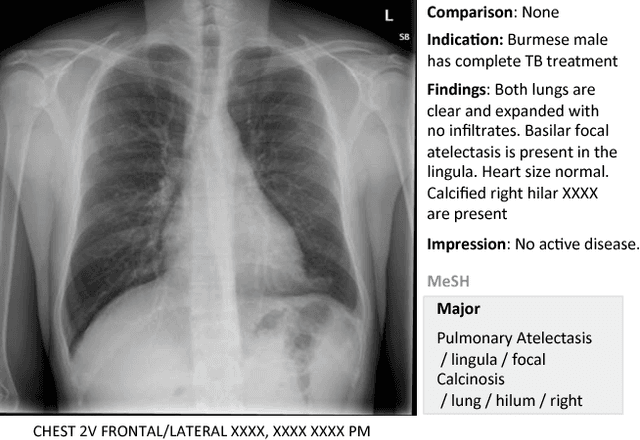

Despite the recent advances in automatically describing image contents, their applications have been mostly limited to image caption datasets containing natural images (e.g., Flickr 30k, MSCOCO). In this paper, we present a deep learning model to efficiently detect a disease from an image and annotate its contexts (e.g., location, severity and the affected organs). We employ a publicly available radiology dataset of chest x-rays and their reports, and use its image annotations to mine disease names to train convolutional neural networks (CNNs). In doing so, we adopt various regularization techniques to circumvent the large normal-vs-diseased cases bias. Recurrent neural networks (RNNs) are then trained to describe the contexts of a detected disease, based on the deep CNN features. Moreover, we introduce a novel approach to use the weights of the already trained pair of CNN/RNN on the domain-specific image/text dataset, to infer the joint image/text contexts for composite image labeling. Significantly improved image annotation results are demonstrated using the recurrent neural cascade model by taking the joint image/text contexts into account.